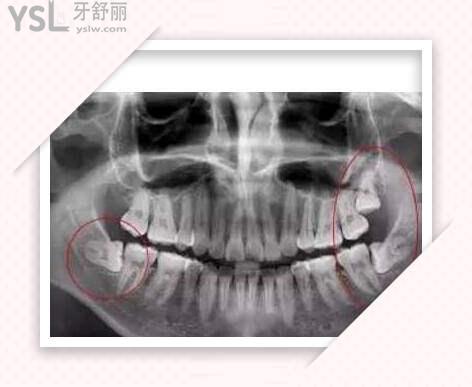

我一直不知道自己有顆智齒,它突然發(fā)炎了。不得已去拔除。先是拍片檢查。然后確定方案,打麻藥過(guò)程就不詳述了,總之弄了一上午。要注意不能做吞咽動(dòng)作又給了止痛藥。過(guò)幾天再去復(fù)診,醫(yī)生技術(shù)還是不錯(cuò)的。

智齒